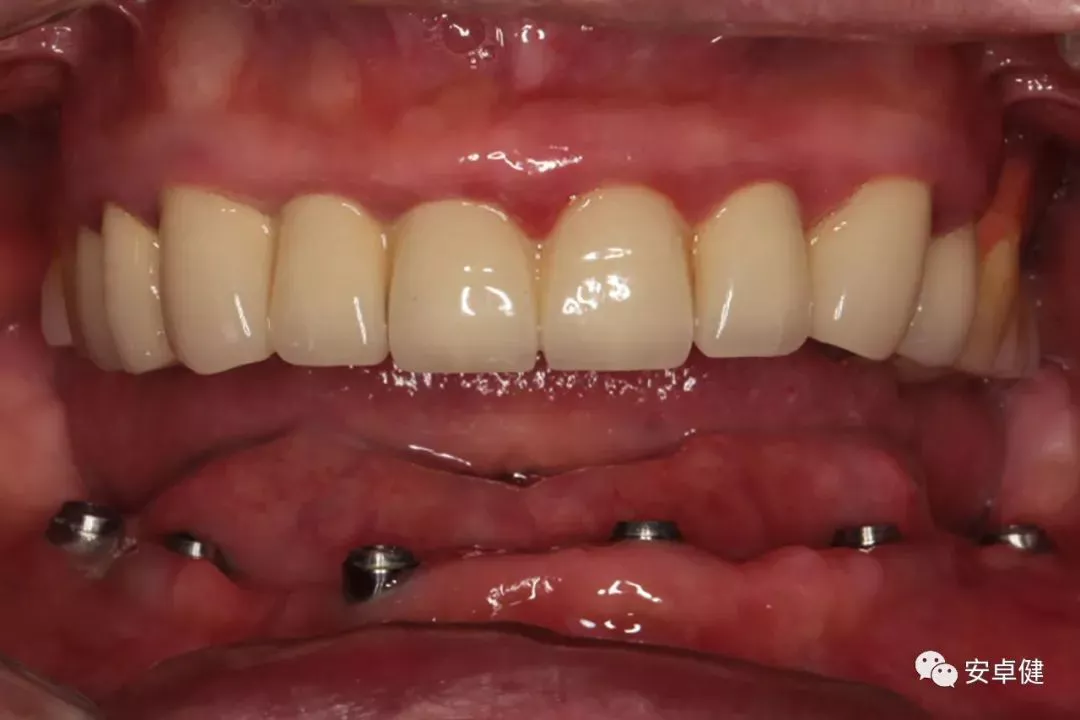

最终修复体合面照

最终修复体正面照

最终修复体正面咬合照

最终修复体侧面咬合照

最终修复复诊合面观

戴最终修复体合面观

戴最终修复体正面咬合照

▷ 永久修复

患者术后16个月:

• 于口内试戴原厂纯钛切削一体式桥架,并检查前牙排蜡外形及后牙咬合关系;

• 聚合瓷烤塑制作最终修复体;

• 为减少牙面磨耗,于后牙区制作360度防裂纯钛金属带;

• 试戴满意后,二级螺丝加力至15N;

• 特氟龙封闭螺丝孔,光固化复合树脂封闭上方螺丝通道,完成最终固定式种植义齿修复;

• 修复体外形能够正确恢复面下1/3高度及侧貌;

• 患者可获得较为稳定的咬合关系,并满足其咀嚼功能的需求;

• 患者42、46部位牙龈退缩,缺乏足够的角化龈,为方便后期清洁维护,选择穿龈较高的龈上肩台;

• 口内观察,修复体边缘金属基台颜色暴露,但由于其处于下颌后牙非微笑暴露区,故对临床整体美观效果的影响在患者可接受范围内。